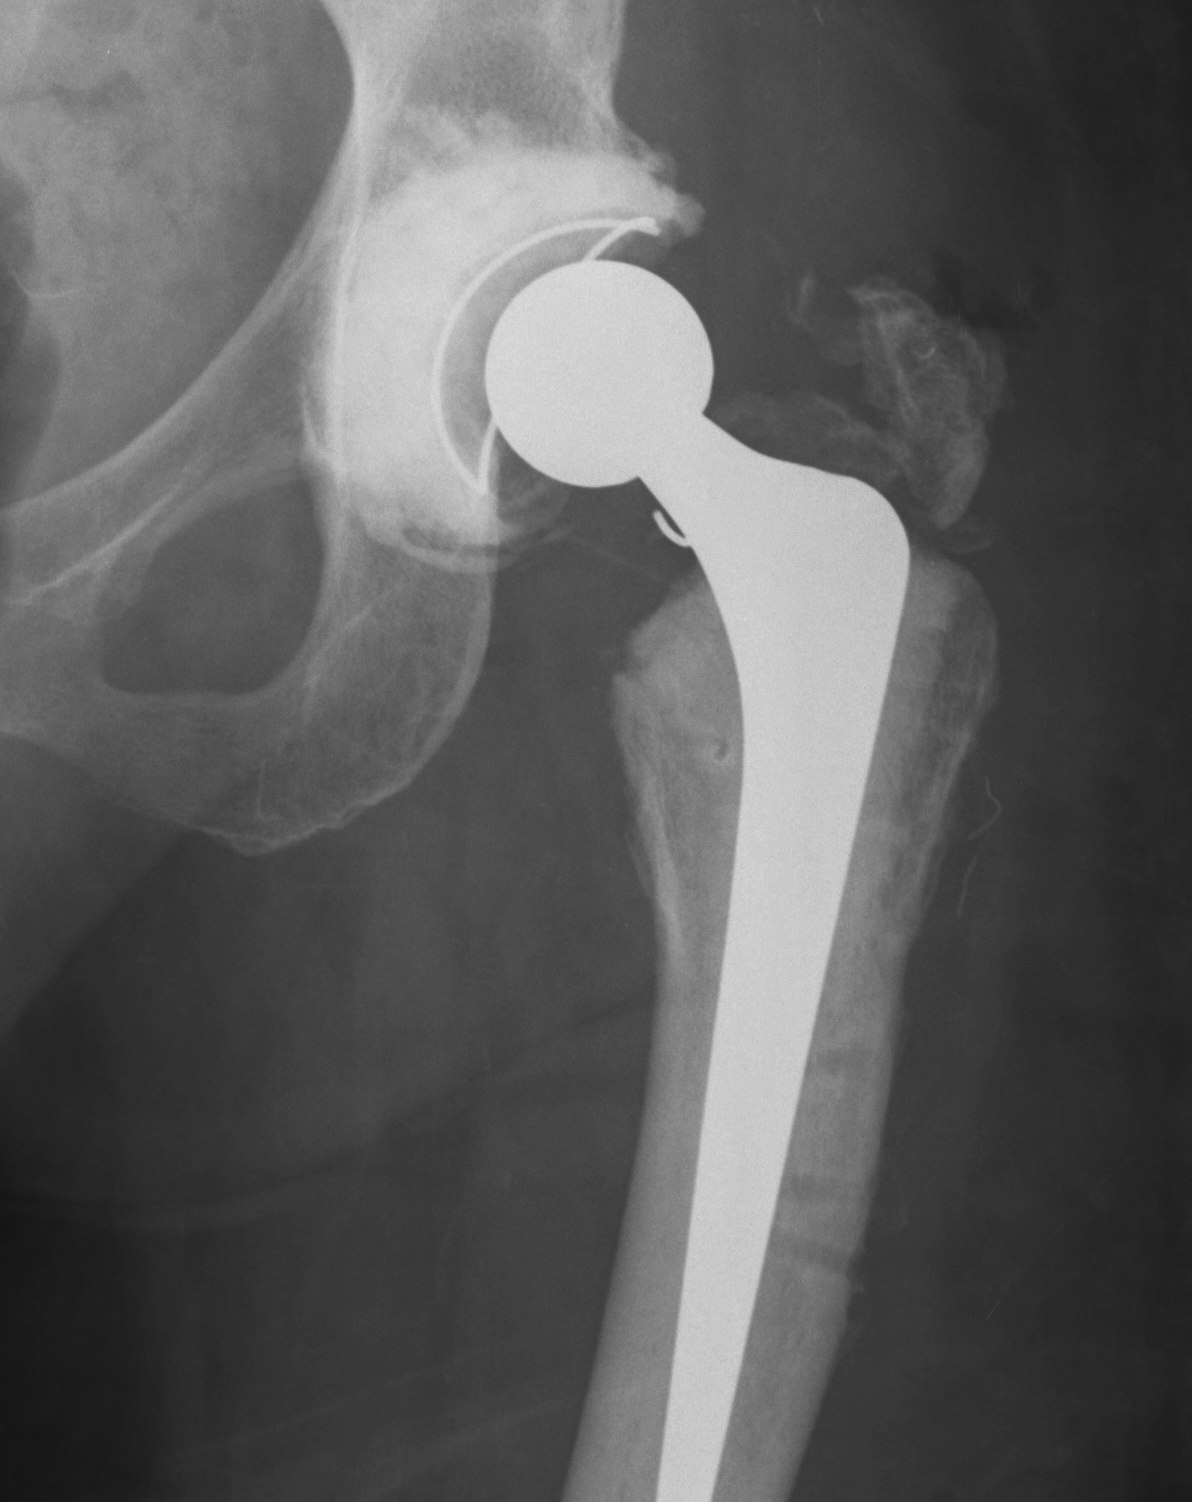

Long stem cemented revision